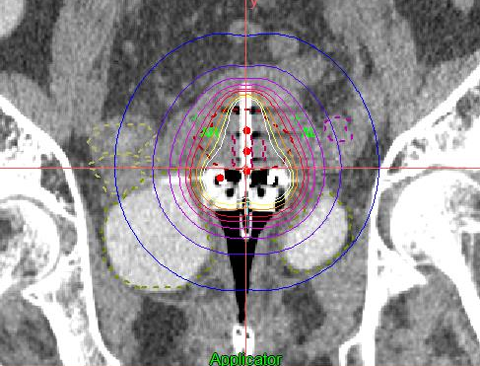

腔内照射では、子宮および腟の中に専用の器具であるアプリケーターを挿入し、体の内部から腫瘍に対して強い放射線を照射することが可能です。外部照射と組み合わせることで、腫瘍局所の制御率を大幅に向上させることが期待できます。

従来は2方向からのレントゲン撮影による2次元治療計画が行われていましたが、現在、当院ではアプリケーターを挿入したままCT画像を撮影できます。この画像を使って、3次元治療計画を行うI G B Tを実施しています。

レントゲンよりも臓器が見えるため、腫瘍にしっかりと放射線を照射しながら、正常臓器の線量を低減することが可能です。